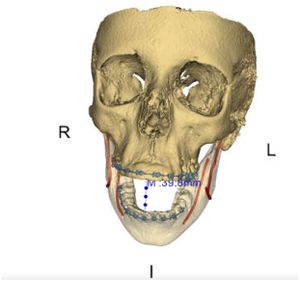

Patient-specific Interactive Software Module for Virtual Preoperative Planning and Visualization of Pedicle Screw Entry Point and Trajectories in Spine Surgery

Publication: Neurol India. 2018 Nov-Dec;66(6):1766-70. PMID: 30504578 | PDF Authors: Muralidharan V, Swaminathan G, Devadhas D, Joseph BV. Institution: Department of Neurological Sciences, Christian Medical College, Vellore, Tamil Nadu, India. Abstract: BACKGROUND: Lumbar pedicle screw insertion involves a steep learning curve for novice spine surgeons and requires image guidance or navigation. Small volume centers may be handicapped by the lack of cost-effective user-friendly tools for preoperative planning, guidance, and decision making. OBJECTIVE: We describe a patient-specific interactive software module, pedicle screw simulator (PSS), for virtual preoperative planning to determine the entry point and visualize the trajectories of pedicle screws. MATERIALS AND METHODS: The PSS was coded in Python for use in an open source image processing software, 3D Slicer. Preoperative computed tomography (CT) data of each subject was loaded into this module. The entry-target (ET) mode calculates the ideal angle from the entry point through the widest section of the pedicle to the desired target in the vertebral body. The entry-angle (EA) mode projects the screw trajectory from the desired entry point at a desired angle. The performance of this software was tested using CT data from four subjects. RESULTS: PSS provided a quantitative and qualitative feedback preoperatively to the surgeon about the entry point and trajectories of pedicle screws. It also enabled the surgeons to visualize and predict the pedicle breach with various trajectories. CONCLUSION: This interactive software module aids in understanding and correcting the orientation of each vertebra in three-dimensions, to identify the ideal entry points, angles of insertion and trajectories for pedicle screw insertion to suit the local anatomy. |

EA mode of pedicle screw trajectory planning in a patient with high grade L5-S1 spondylolisthesis. (a) Correction of vertebra rotation. (b) Marking of fiducials. (c) Desired trajectory for selected entry point and angle. (d) Marking of the entry and target fiducials for desired iliac wing screw. (e) Ideal trajectory of iliac wing screw and panel displaying the angle of screw trajectory using entry-target mode. |